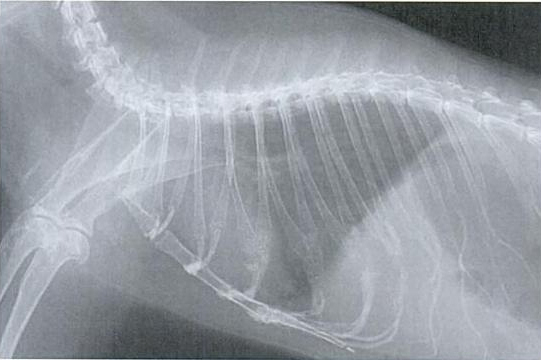

Slike dišnih puteva bez oboljenja:

Nedostatak tipičnih simptoma često otežava ranu dijagnozu. U slučaju bolesti se provode kliničke pretrage kao slušanje, mjerenje temperature, pulsa i promatranje frekvencije disanja. RTG pregled je koristan u slučaju dileme. Može pokazati da li i u kojem obimu postoje sjene u predjelu pluća. Kako se uzročnik ne može razlikovati, trebalo bi dati sekret iz nosa ili očiju, ili bris grla tj. nosa na pretrage kako bi se ustanovila kultura uzročnika i napravi antibiogram. U slučaju smrti, naročito ako je više životinja zaraženo, obdukcija bi imala smisla.